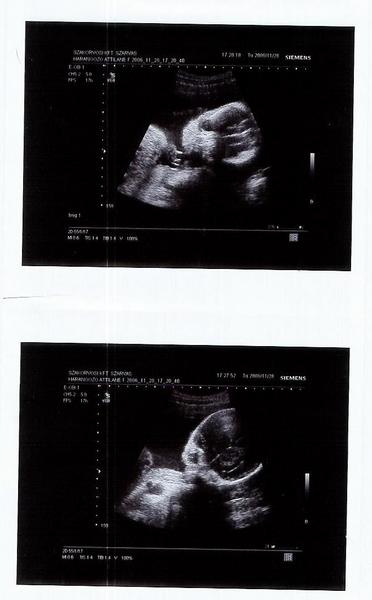

Kisherczeg! Nagyon szép babátok lesz! Már most látszik! Nektek sincs már sok hátra!